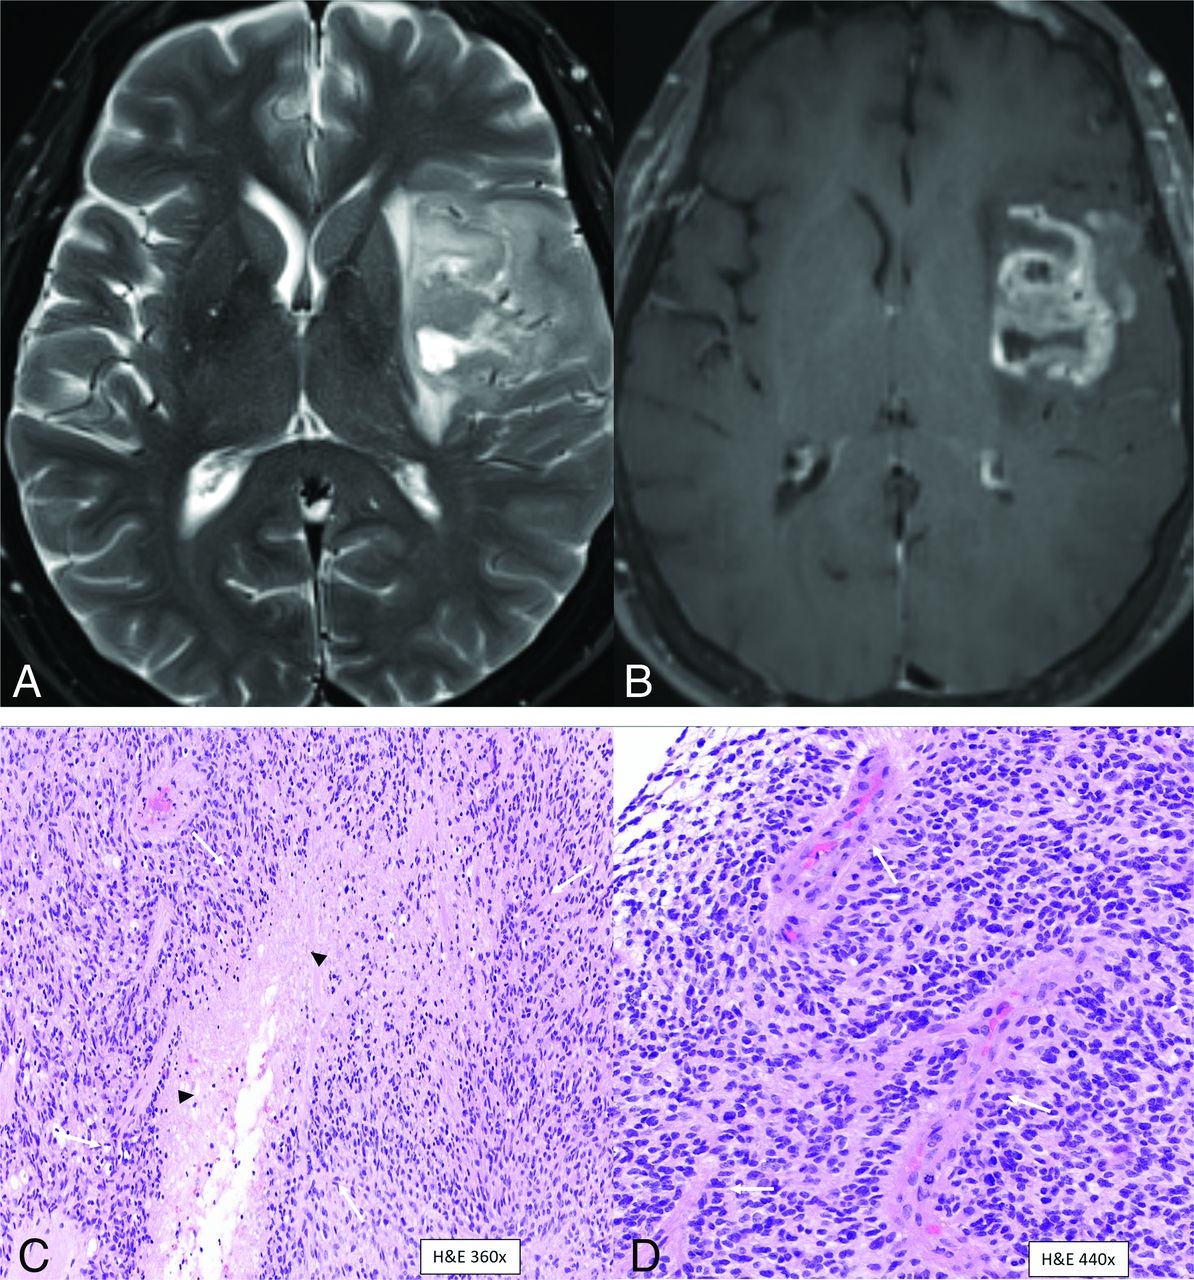

MR imaging revealed a well-circumscribed T2/FLAIR hyperintense cortical-subcortical mass centered in the frontal operculum with minimal edema, no T2/FLAIR mismatch, and no necrotic changes (Fig 1A, -B). No hemorrhagic changes or calcification was noted on the SWI (Fig 1C). The tumor showed diffuse hyperintensity on DWI with areas of low ADC values along the periphery of the mass (Fig 1D, -E). A contrast-enhanced image (Fig 1F) showed minimal patchy enhancement within the mass. Perfusion study was not performed. Primary imaging differential was a low-grade glioma (likely oligodendroglioma) and neurosurgical consult was recommended.

Left frontal lobe mass in a 39-year-old man with histologic low grade (WHO grade 2) and positive chromosomal 7 and 10 mutations supporting the molecular profile of “Glioblastoma, IDH-wild-type (CNS WHO grade 4).” Multiple axial MR images reveal a well circumscribed T2/FLAIR hyperintense cortical-subcortical mass (A and B, arrows) involving the frontal operculum with minimal edema and no internal necrotic changes. No hemorrhagic changes are noted on the SWI (C). DWI (D) and ADC map (E) reveal area of restricted diffusion with low ADC vales along the periphery of the mass. Contrast-enhanced image (F) shows minimal patchy enhancement within the mass.